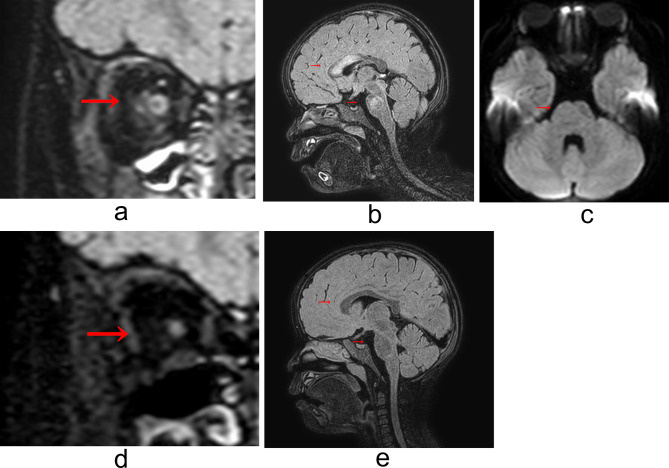

Efficacy of mycophenolate mofetil for the maintenance therapy of anti-AQP4 antibody-positive NMOSD complying with probable sjögren's disease in a 2-year-old girl: a case report.